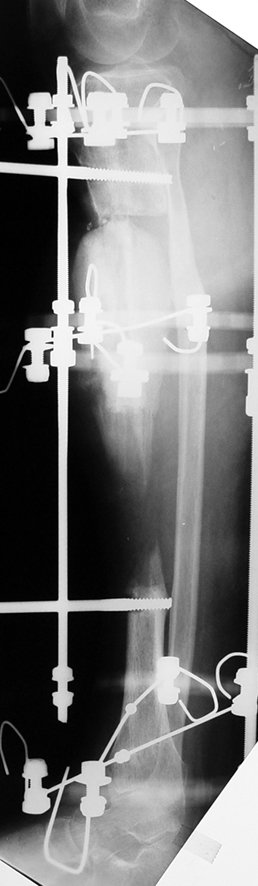

Recently, ilizarov techniques which is basis depend on distraction osteogenesis , bone segment transport or acute shortening after the resection at the site of pseudarthrosis combined with lengthening at another level of bone have been used. These treatment techniques may include some advantage for problems of infection, leg-length discrepancy, soft-tissue loss, and joint contracture.

Case 1